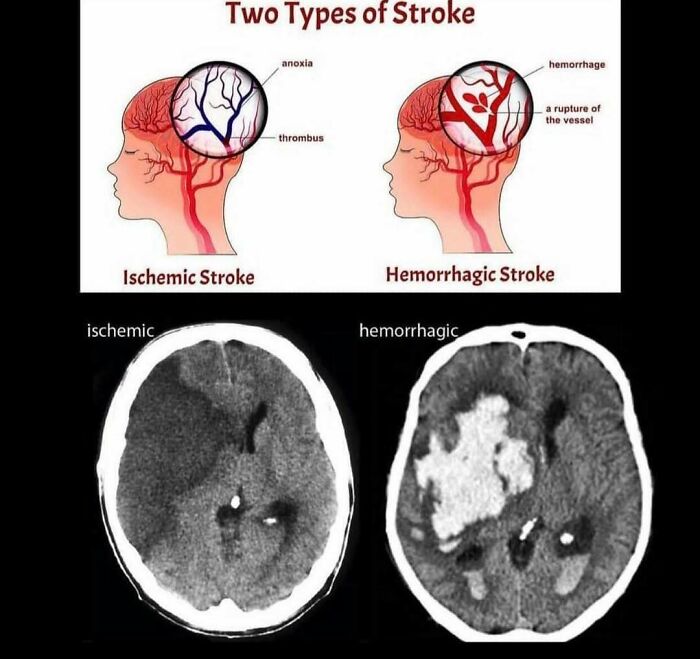

I had a "pinpoint" ischemic stroke over a decade ago that caused permanent visual field loss in my left eye. Immediately following the stroke [not that I knew it was a stroke at the time], I actually lost the "ability" to process colors properly, so I had a weird form of colorblindness (purples and blues looked gray to me, green looked brown/orange, and I couldn't distinguish between shades of red, orange, and yellow at all.) Luckily the color issues resolved months later, but the vision loss remained.